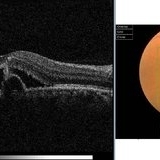

Macular Pseudohole Macular PseudoholeJul 7 2015 by Hamid Ahmadieh, MD Color fundus photograph and optical coherence tomography of the left eye of a 72-year-old woman with blurred vision due to epiretinal membrane. VA OS is 20/40 . Macular pseudohole is visible. Photographer: Shabnam Poureh, Negah Eye Center, Tehran, Iran Imaging device: Topcn Condition/keywords: color fundus photograph, macular pseudohole, optical coherence tomography (OCT)